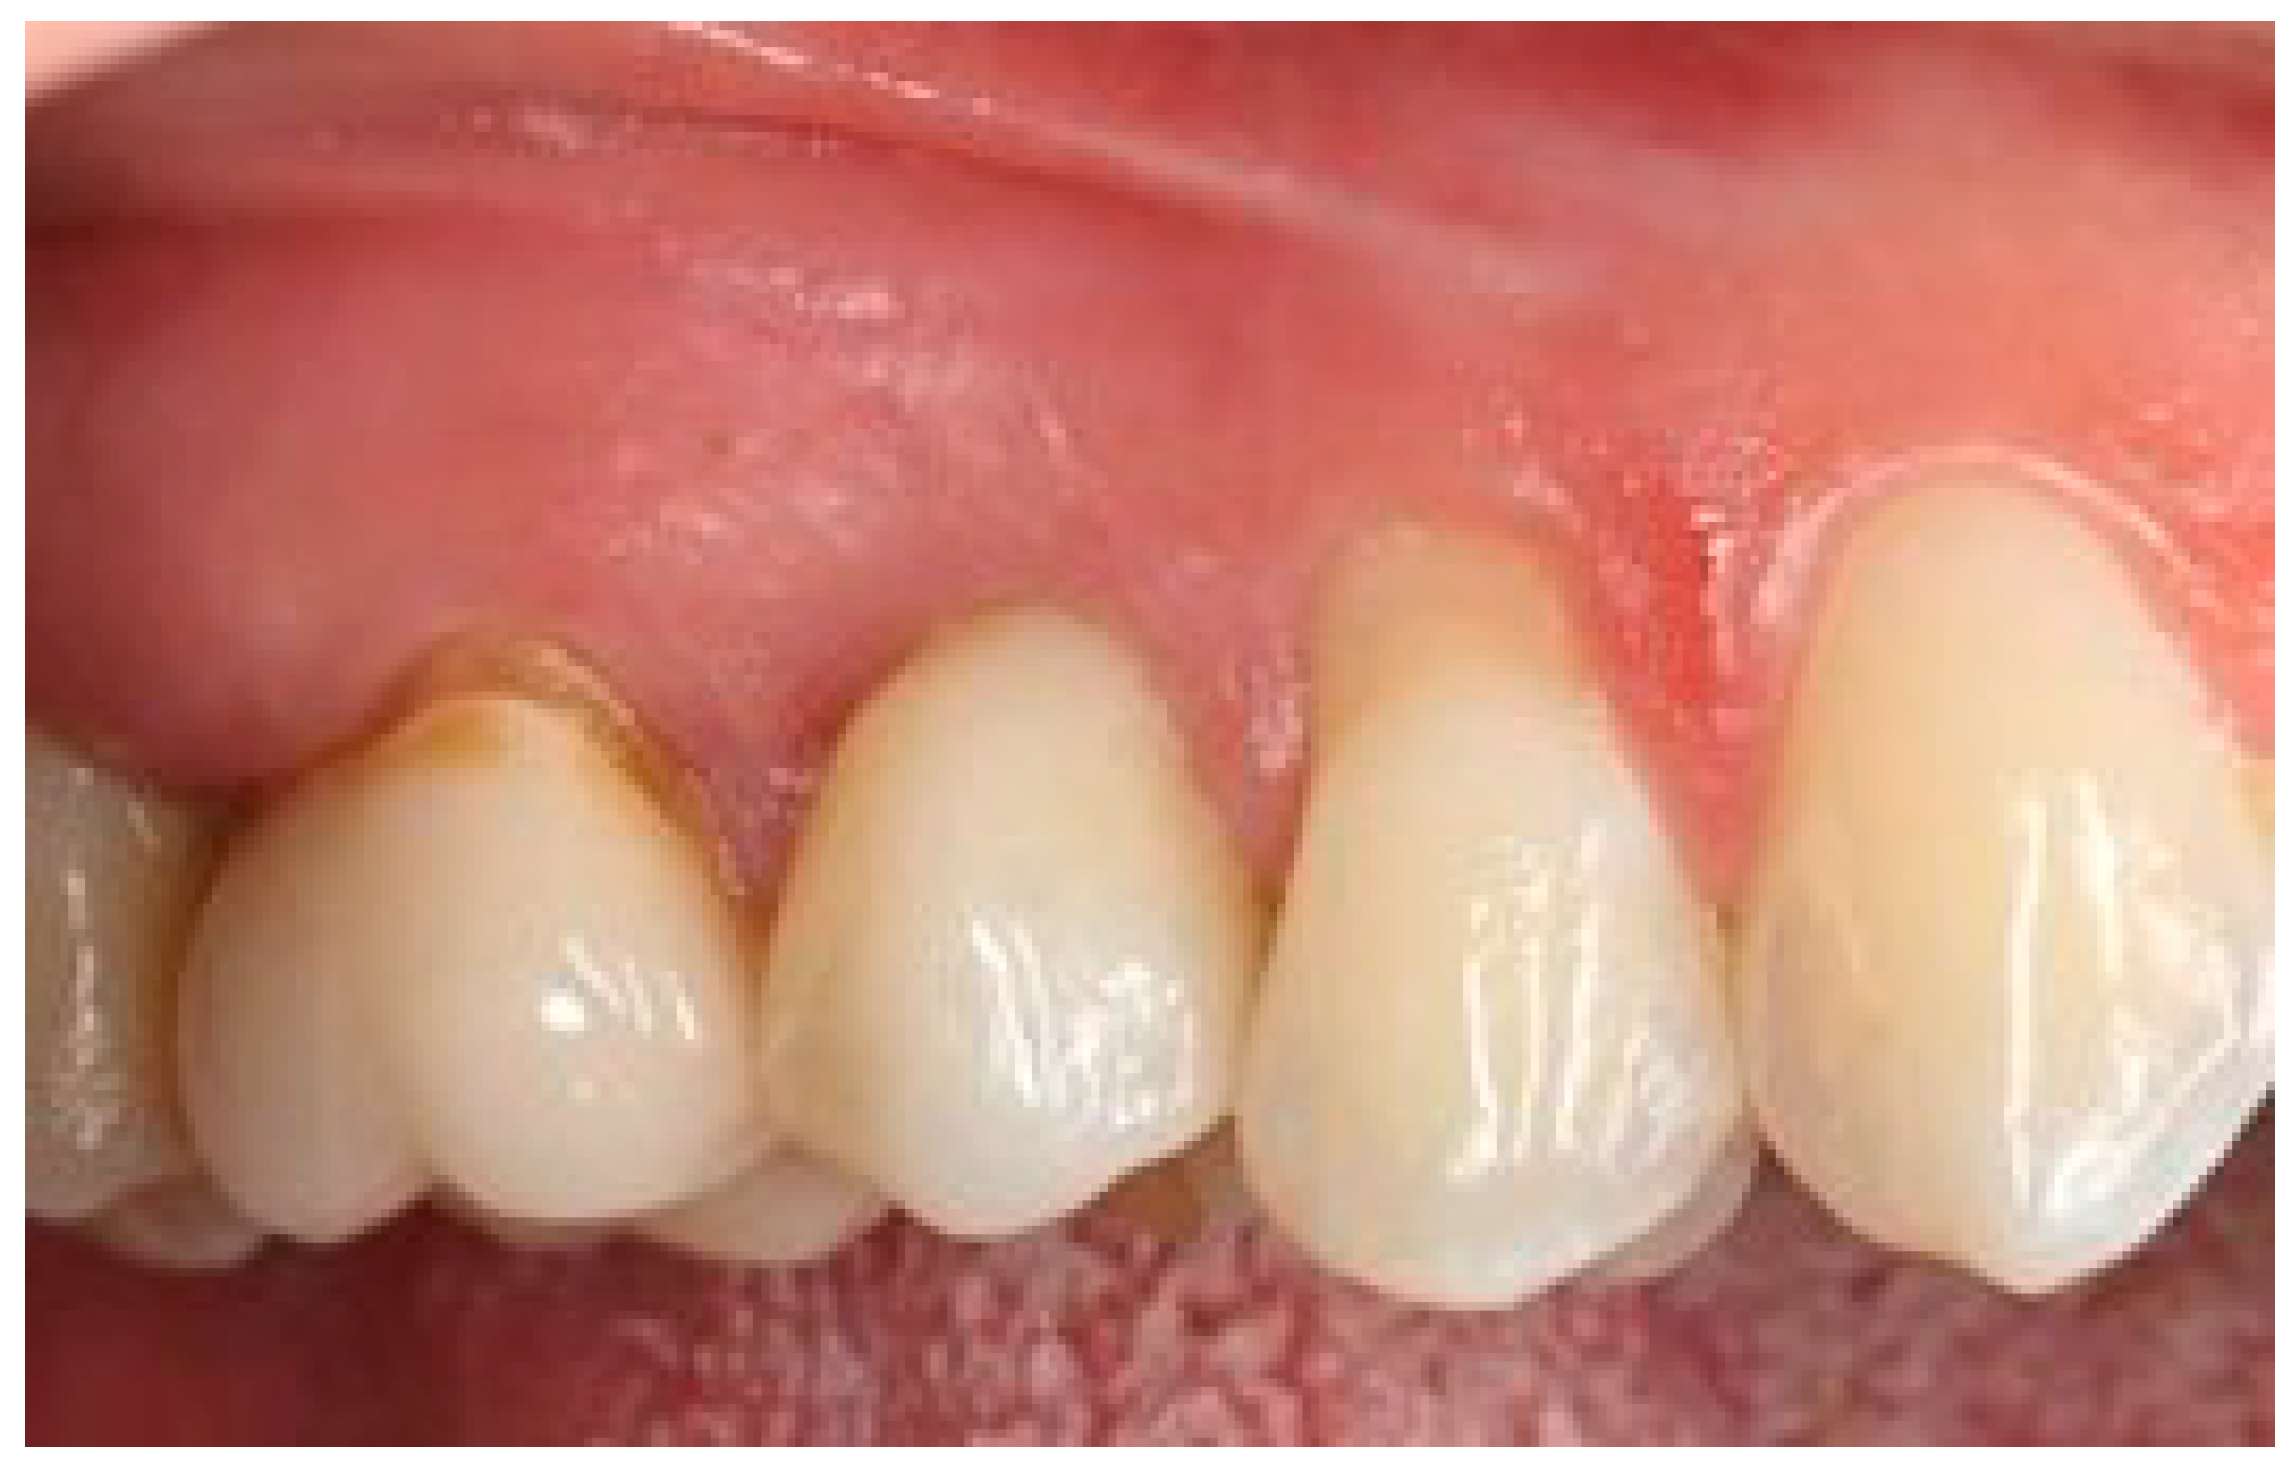

Figure 14 visualizes the mean distance between the soft tissue margin and fixture surface over time, from three months (T1) to 5 years (T3), for both the test and control groups. The error bars represent the standard deviation for each mean value, providing a visual representation of the variability within each group at each time point. At baseline and 3 months, there were no significant differences between the test and control groups (p > 0.05). At 1 year and 5 years, the test group showed significantly smaller distances compared to the control group (p < 0.01 and p < 0.001, respectively). The test group demonstrated a gradual decrease in distance over time, while the control group showed a slight increase. The clinical aspects are shown in Figure 15 and Figure 16.

Figure 15.

One-year follow-up. Element 1.5.

Figure 16.

Five-year follow-up. Element 1.5 of the same patient.